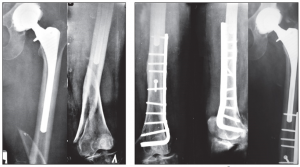

Радиологиялық зерттеу. Алдыңғы және бүйір проекциядағы жақындағы қантамырларды қоса алумен жүргізілетін рентгенография сынық сипатын бағалауға көмектеседі. Басқа радиологиялық зерттеулер жүргізудің қажеті жоқ.

Ұршық асты және айдаршық үсті сынықтарының остеосинтезі үшін жиі бұрышты пластина немесе накладкасы бар динамикалық винт қолданылады. Ортаңғы үштен бір бөлігінің сынығында пластинамен экстрамедуллярлы остеосинтез немесе штифпен интрамедуллярлы остеосинтез жүргізіледі. Стерженьдік аппарат көмегімен фиксациялауға да болады.

Диафиз сынығының стабильды остеосинтезңне құм сағаты формалы сүйекми каналының біркелкі емес ені бөгет жасайды. Штифт тек қана каналдың арылу аймағында ғана жанасып жатады. Егер сынық аймағына сүйекми каналының тарылу аймағы сәйкес келмесе сынықшалар арасында ротационды және тербелмелі қозғалыстар тән. Стабильді остеосинтез жасау үшін сынық орнында сүйекми каналын штифтпен бірдей қылып бұрғылайды. Сәйкес диамитрлі штифт енгізіледі. Бұрғылаусыз стабильды остеосинтез үшін дистальды және проксимальды блоктайтын штифт қолданылады.